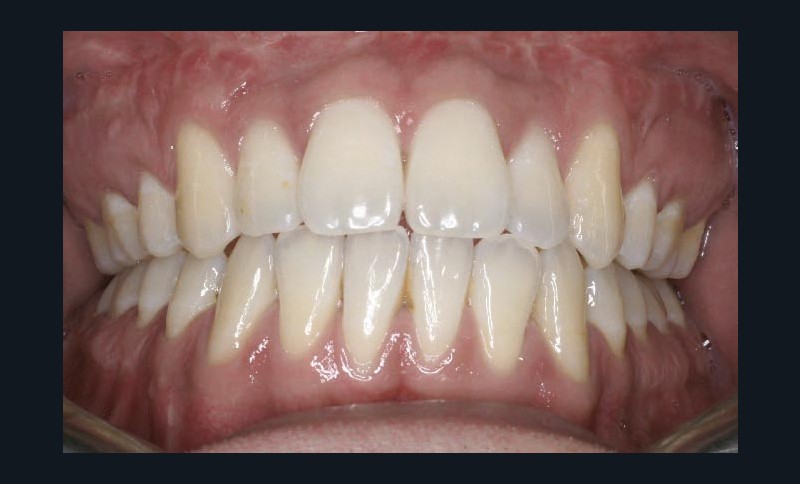

Les résultats esthétiques et occlusaux satisfont amplement le patient qui revient pour un contrôle à long terme 10 ans après l’intervention montrant la stabilité des résultats.